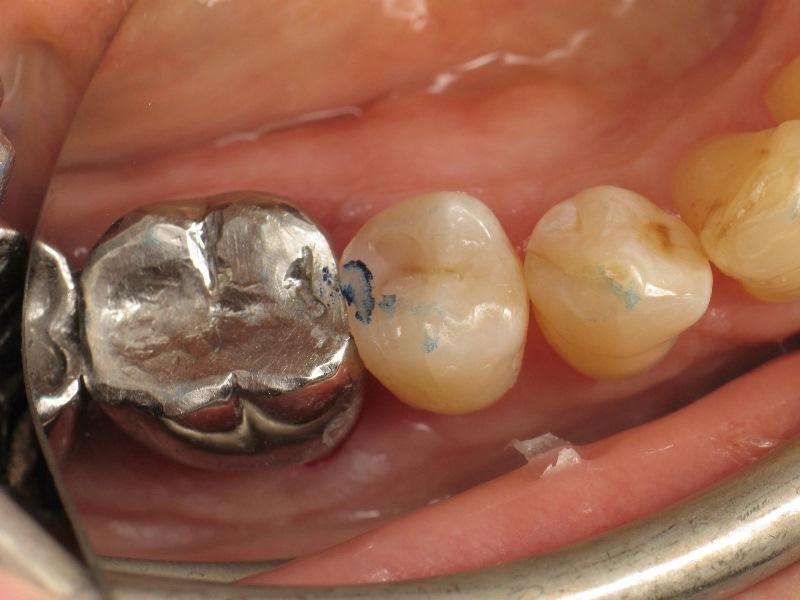

Фото 1. Премоляр с кариесом II класса.